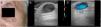

CASO 2: el segundo caso fue un hombre de 72 años con un nódulo translúcido en la sien derecha (fig. 3). El diagnóstico clínico era sugestivo de un hidrocistoma. En la exploración ecográfica también observamos una lesión quística hipoecoica con un flujo turbulento en el Doppler color (fig. 4). El diagnóstico anatomopatológico final fue consistente con el diagnóstico clínico de hidrocistoma.

Chin et al. evaluaron varios hidrocistomas empleando US. Sugirieron que dichas estructuras mostraban una lesión quística con una superficie hiperecoica y un centro hipoecoico (restos de lipofuscina) o un centro ecolúcido (líquido claro)3. Perez-Lopez et al. insistieron en la ausencia de flujo dentro de estas estructuras4. Sin embargo, en nuestros casos hemos visto que a veces estas estructuras pueden mostrar una señal Doppler positiva.

El pseudoflujo es un artefacto Doppler relacionado con el movimiento de otro líquido diferente a la sangre en ausencia de una estructura vascular, y se asemeja al flujo real de sangre en el Doppler color o en el power Doppler. La señal del Doppler color o del power Doppler aparecerá mientras se mantenga el movimiento del fluido. Sin embargo, si usamos el análisis espectral, este mostrará un patrón inconsistente con el flujo vascular2.

En nuestros casos, el movimiento del material en el interior del hidrocistoma condujo a una imagen en el Doppler color que puede interpretarse incorrectamente como flujo vascular.